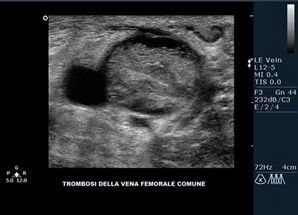

Diversa è la situazione se il coagulo di sangue si forma in una vena che è essa stessa il vero sistema di ritorno venoso dell’arto, ovvero del sangue che dal piede torna verso il cuore. Negli arti inferiori possono essere coinvolte: le vene tibiali e le gemellari (TVP distale); la poplitea, le femorali, le iliache (TVP prossimale). Se si forma un coagulo in queste vene, le manifestazioni sono diverse e si presenta un quadro clinico più serio rispetto alla TVS, possiamo assistere più frequentemente alla embolizzazione polmonare anche massiva con morte improvvisa. Il quadro clinico della TVP dell’arto è caratterizzato dalla comparsa di gonfiore (edema), calore, dolore.

La diagnosi può essere clinica ma deve essere confermata da un ecocolordoppler: si può verificare lo scorrimento del sangue nella vena e se è comprimibile o meno (compressione ultrasonografica - CUS). Se non si comprime, è presente un coagulo.